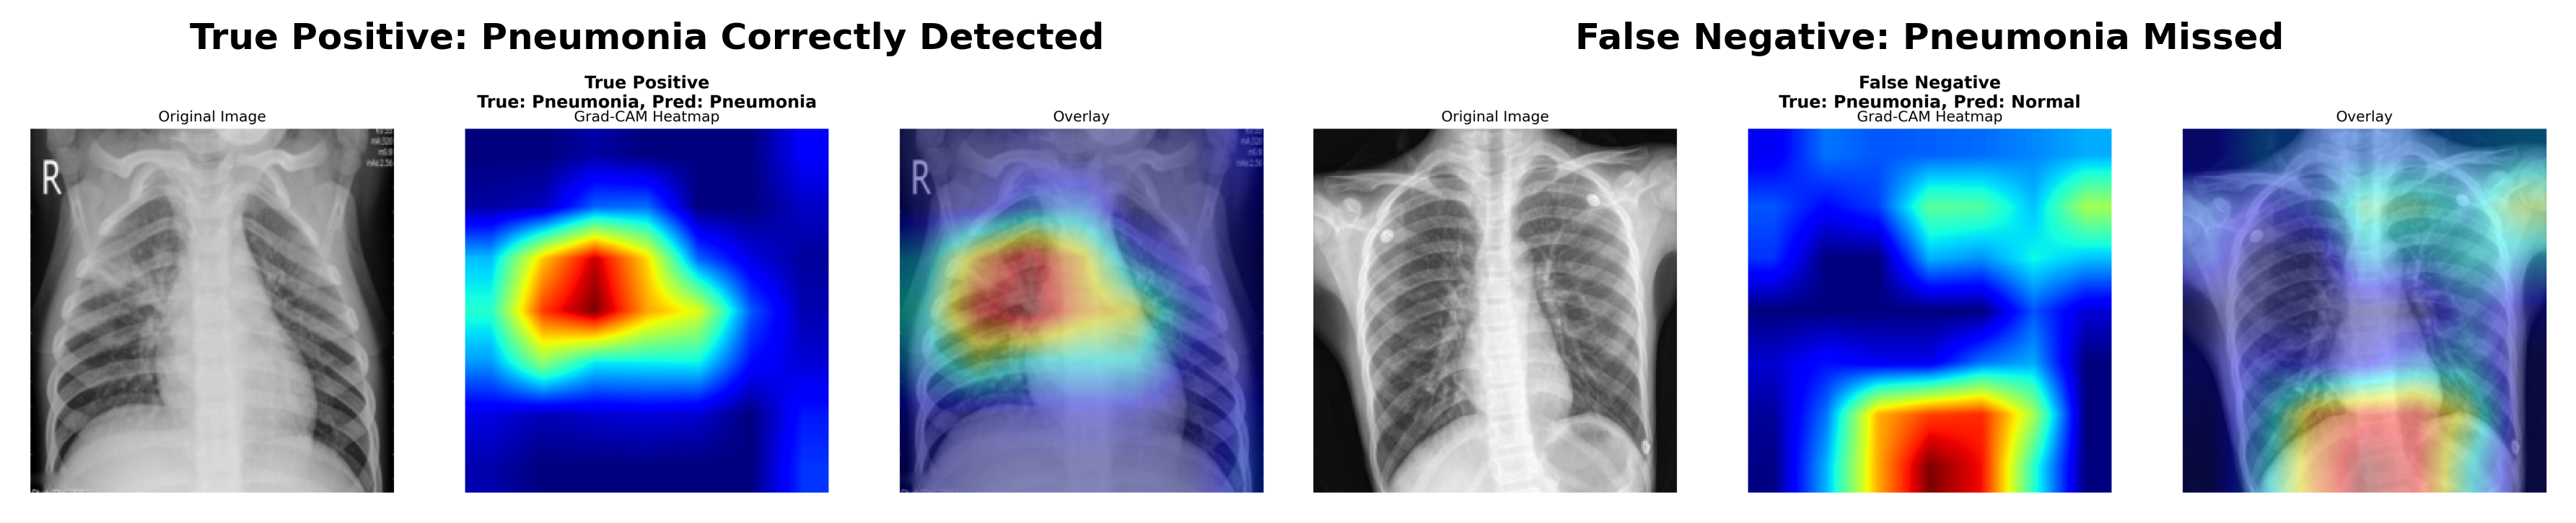

Grad-CAM visualizations revealed that all models focus on clinically relevant regions. As illustrated in Figure 4, Grad-CAM highlights lung infiltrates in true positive cases while revealing the subtle nature of missed pneumonia in false negative cases.

True Positive Cases: Models consistently focused on lung infiltrates, consolidations, and areas of increased opacity—features used by radiologists for pneumonia diagnosis.

False Negative Cases: The 2 false negatives from ResNet50 involved subtle infiltrates that may be challenging even for expert radiologists.

Refer to caption

Figure 4: Grad-CAM visualizations for ResNet50 (fine-tuned) showing model attention patterns. Left: True Positive case where the model correctly identifies pneumonia by focusing on lung infiltrates and opacities. Right: False Negative case where subtle infiltrates were missed, representing one of only 2 errors out of 388 pneumonia cases.